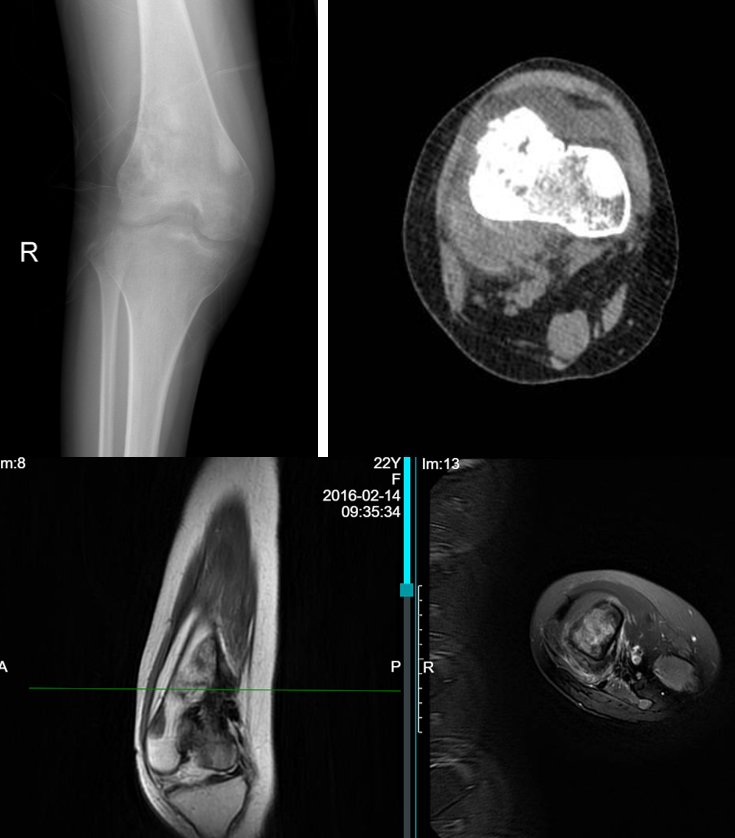

女性,22岁,因为右膝关节疼痛2周余就诊,在外院X线摄片发现右侧股骨下段肿瘤。磁共振显示右侧股骨下段恶性骨肿瘤。至我院就诊,在X线摄片上可以看到在右侧股骨下段有局部肿瘤骨形成,密度较高,同时也能看到虫蚀样骨质破坏。磁共振图像也提示T1和T2加权都是低信号的肿瘤骨和T1低信号T2高信号的软组织肿物。

图示:术前影像